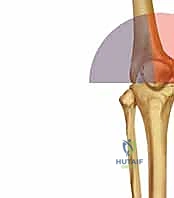

التشريح المعقد والميكانيكا الحيوية لعظم الفخذ ومفصل الركبة

لفهم مدى تعقيد هذه الكسور، يجب أن نغوص في التشريح الدقيق لهذه المنطقة. يمثل الجزء السفلي من عظم الفخذ نقطة الارتكاز الأساسية لوزن الجسم أثناء الحركة والوقوف.

يمر المحور الميكانيكي لعظم الفخذ من مركز رأس عظم الفخذ إلى مركز الركبة، وعادة ما ينحرف بمقدار 3 درجات عن الخط العمودي. يستمر هذا المحور بعد ذلك إلى مركز الكاحل، ليحدد المحور الميكانيكي للطرف بأكمله. في المقابل، يظهر المحور التشريحي لعظم الفخذ مع حوالي 9 درجات من الانحراف الخارجي (Valgus) بالنسبة لمحور مفصل الركبة.

عند حدوث كسر في هذه المنطقة، تختل هذه المحاور الدقيقة، مما يؤدي إلى توزيع غير متساوٍ للضغط على غضاريف الركبة. إذا لم يتم إصلاح هذا الخلل جراحياً بدقة متناهية، فإن المريض سيكون عرضة للإصابة بخشونة الركبة المبكرة (Post-traumatic Osteoarthritis).